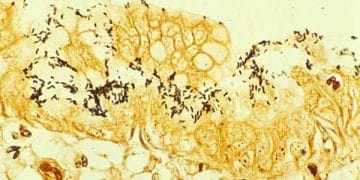

Warthin-Starry Gümüş Boyası, Bartonella ve spiroketlerin boyanmasında kullanılan, yaymalarda ve doku kesitlerine uygulanan boyama yöntemine denir. Warthin-Starry Silver Stain